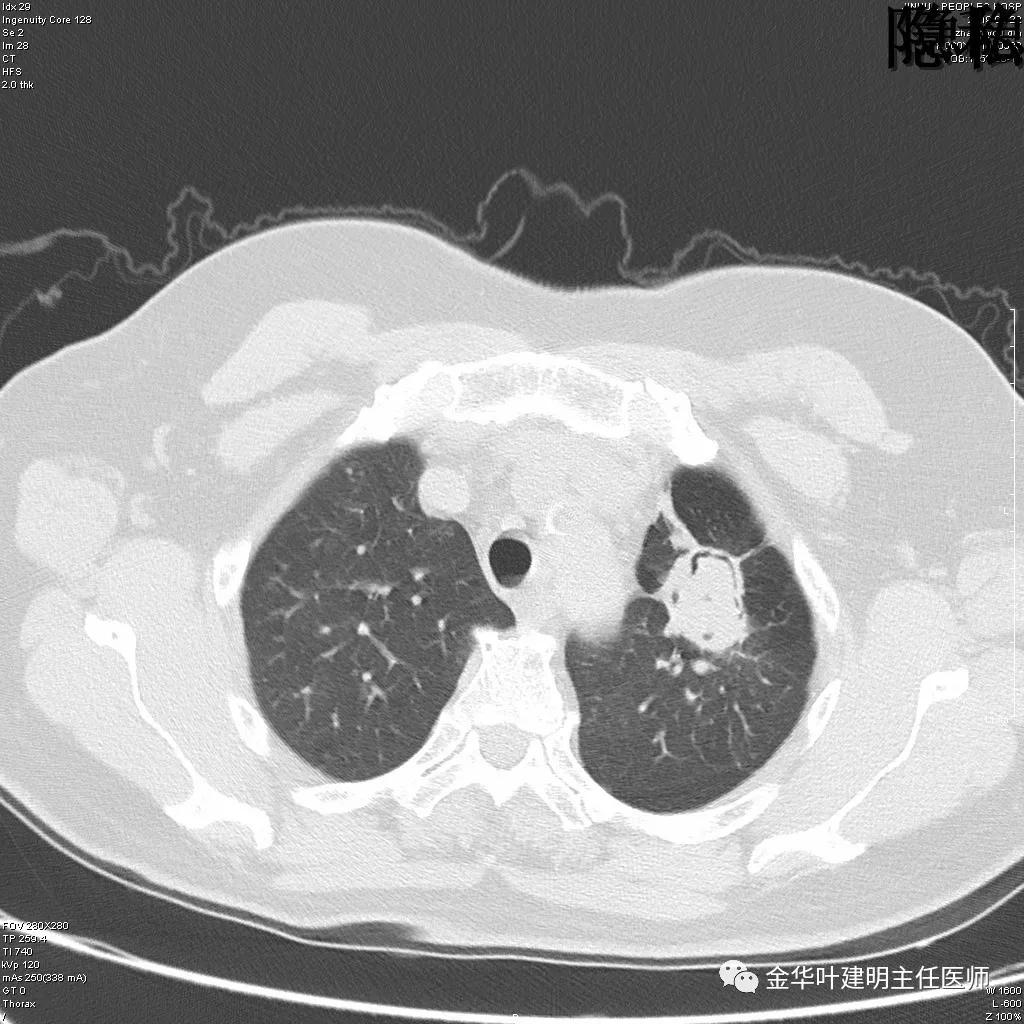

可见左肺下叶比较靠中央的部位也有一病灶,是混合磨玻璃影,偏实性,瘤肺边界清楚,是较为典型的肺癌表现。进一步的靶扫描图像如下:

靶扫描更清晰的显示细节,从影像上看,基本可以断定左下肺的是恶性肿瘤了,而且已经密度较高,长径也在3厘米以上,不能继续观察等待了!